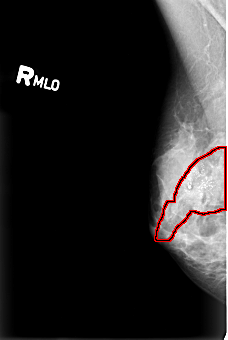

B_3008_1.RIGHT_MLO

RIGHT_MLO LINES 4408 PIXELS_PER_LINE 2952 BITS_PER_PIXEL 12 RESOLUTION 50 OVERLAY

FILE: B_3008_1.RIGHT_MLO.OVERLAY

TOTAL_ABNORMALITIES 1

ABNORMALITY 1

LESION_TYPE CALCIFICATION TYPE PLEOMORPHIC DISTRIBUTION REGIONAL

ASSESSMENT 5

SUBTLETY 5

PATHOLOGY MALIGNANT

TOTAL_OUTLINES 1

BOUNDARY